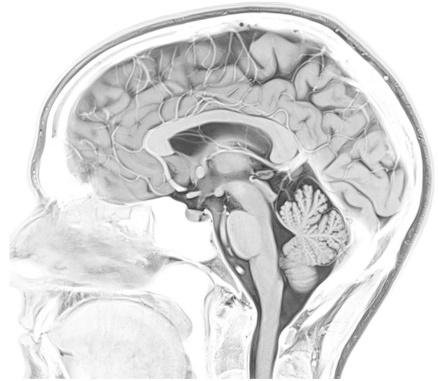

Project Title: Postmortem MR imaging of the human brain - mapping disease related changes

With this project we wish to optimize an MR imaging sequence for 3T scanning of postmortem human brain hemispheres and develop an image analysis pipeline for parcellation of brain regions with the aim to quantify regional volumes and surfaces.

Postmortem scanning of human brain tissue is an important tool to screen for disease related changes to regional volumes or microstructures of the brain. Further, it significantly enhances the value of downstream histological or molecular studies, as it allows for co-registrering results from small fields of view < 1 cm2 with the 3D context from which they were sampled. The Allen Brain atlas is a prime example of how combining MRI and histology may accelerate our understanding of the human brain. We want to be able to do that for mapping neurodegenerative diseases. However, tissue contrasts changes when tissues are fixated In this project, you will work on tailoring the imaging parameters/sequences and the data analysis methods to achieve accurate registration and segmentation of the postmortem MRI data.